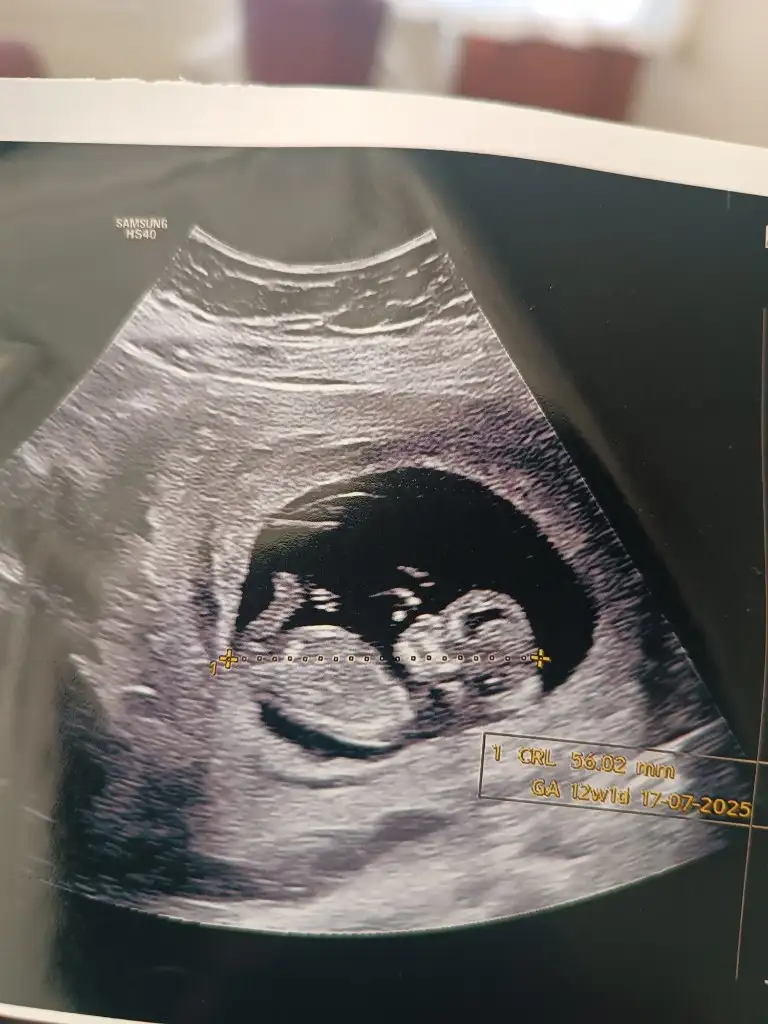

Buda bebişimiz

Cinsiyet tahmininde bulunmadı doktor bende tam soracakken hemen gitti kalkmak zorunda kaldım

Yapabilen arkadaş varsa beklerim

Eklentiler

• IMG_0282.webp

82,7 KB · Görüntüleme: 95